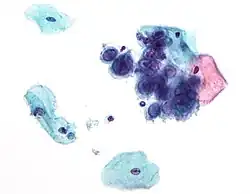

| Chlamydia trachomatis bacteria found in a pap test of the cervix in a case of chlamydia | |